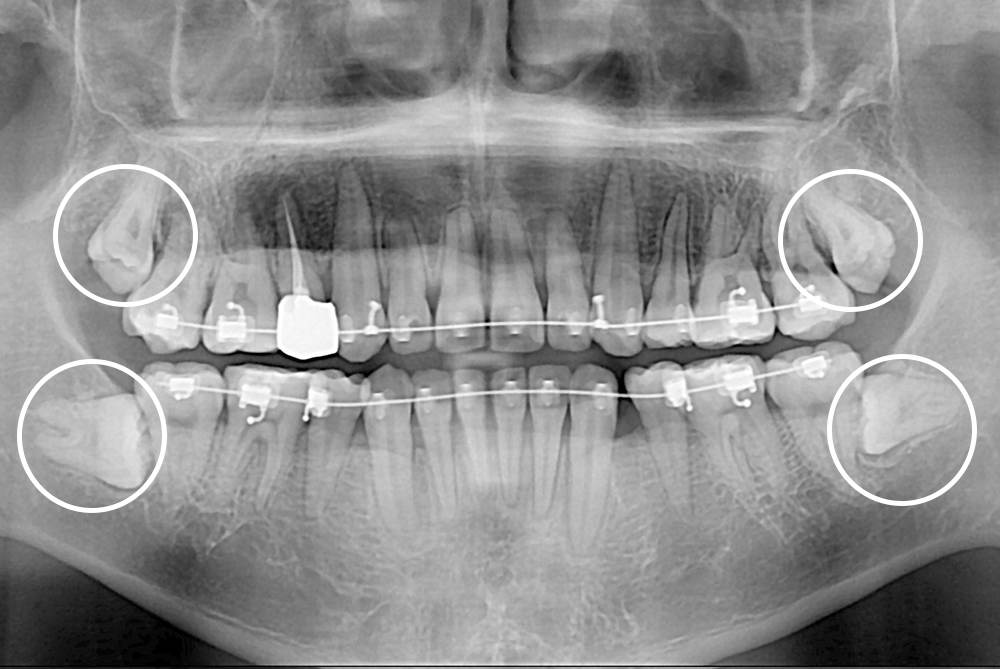

[사랑니] 매복 사랑니 발치

치료후 : 2019-08-14

세종치과는 구강악안면외과학 박사이신 원장님이 발치하는 치과입니다.